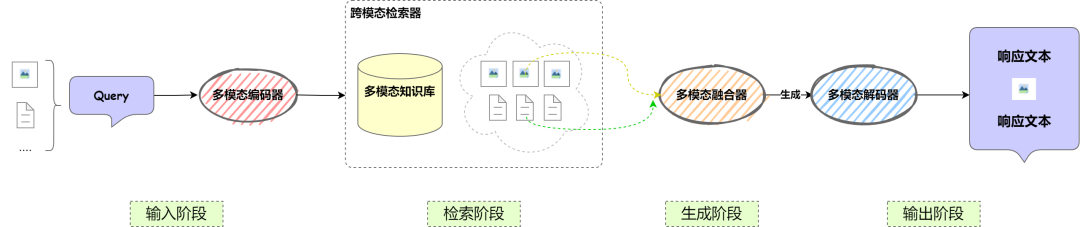

从整体架构出发

👇

No.2

多模态 RAG VS 基础 RAG:升级点大揭秘!

基础的RAG主要针对文本数据进行了检索与生成。然而,要支持多模态输入和输出,需要对基础 RAG 架构进行一定的调整和扩展。

首先,需要修改的模块包括:

📌检索模块:从仅支持文本检索,到需要扩展为支持多模态检索,例如图像、音频等信息的索引和匹配。

📌生成模块:基础 RAG 仅针对文本生成,现在需要扩展支持多模态输出,如文本结合图像、音频的生成能力。

其次,需要新增的模块包括以下四个部分:

📌多模态编码器:用于对不同模态的数据(文本、图像、音频等)进行编码,以便统一表示并用于检索和生成。

📌多模态融合器:用于融合不同模态的信息,使其能够协同作用,提高生成内容的准确性和丰富度。

📌跨模态检索器:支持输入多种数据格式,并能在多模态知识库中找到相关信息。

📌多模态解码器:负责将生成结果解码为多种形式,如文本、图片、语音等,以适应不同的输出需求。

No.3

多模态RAG的核心组件

为了支持多模态输入和输出,调整和扩展后的多模态RAG 流程图如下。

接下来,小编简单讲一下每个组件的功能以及相关输入输出示例哦~👇